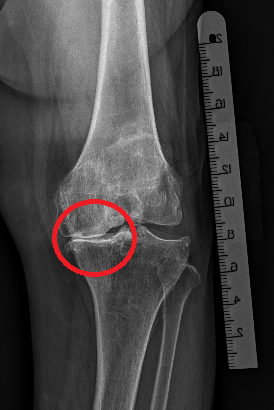

(晚期骨關(guān)節(jié)炎X光片:內(nèi)側(cè)關(guān)節(jié)間隙變窄,骨硬化,骨質(zhì)增生)

其實(shí),像王阿姨這樣的膝關(guān)節(jié)疼痛,醫(yī)學(xué)病名是老年性膝骨性關(guān)節(jié)炎,它是膝關(guān)節(jié)軟骨變性、骨質(zhì)增生而引起的一種慢性骨關(guān)節(jié)疾病。醫(yī)師將老年性膝骨性關(guān)節(jié)炎分為早、中和晚三期。早期表現(xiàn)為膝間歇性活動(dòng)痛,深蹲起立和爬樓爬山時(shí)明顯,X線片檢查多為正常;中期表現(xiàn)膝疼痛的程度和頻率增加,出現(xiàn)腫脹,深蹲起立和爬樓爬山時(shí)疼痛更明顯,X線片檢查關(guān)節(jié)間隙變窄,有增生的骨刺出現(xiàn);晚期表現(xiàn)持續(xù)地膝疼痛、腫脹,畸形,行走、深蹲起立和爬樓爬山因疼痛而非常困難。X線片檢查關(guān)節(jié)間隙變窄、消失,有較多增生的骨刺出現(xiàn)。 治療上,早期主要調(diào)整生活方式,積極進(jìn)行關(guān)節(jié)功能鍛煉,輔助藥物治療;中期主要使用藥物治療;晚期主要是手術(shù)治療,手術(shù)方式主要是全膝關(guān)節(jié)置換術(shù)和微創(chuàng)膝單髁置換手術(shù)。